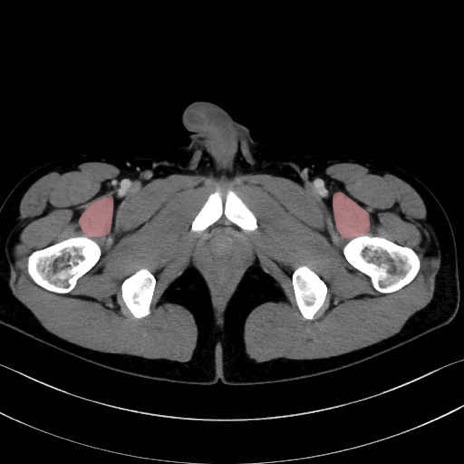

大腿方形筋 (Quadratus femoris)